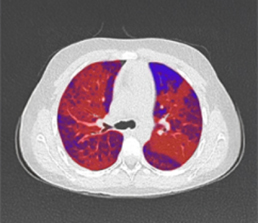

Built on advanced capabilities in lung segmentation and quantification, our AI technology interprets thoracic CT data with anatomical precision - capturing airway trees, parenchymal patterns, and vascular structures, even in severely diseased lungs.

These insights enable next-generation support for minimally invasive interventions across clinical treatment pathways, targeting pulmonary conditions such as emphysema, lung cancer, and chronic airway disease.